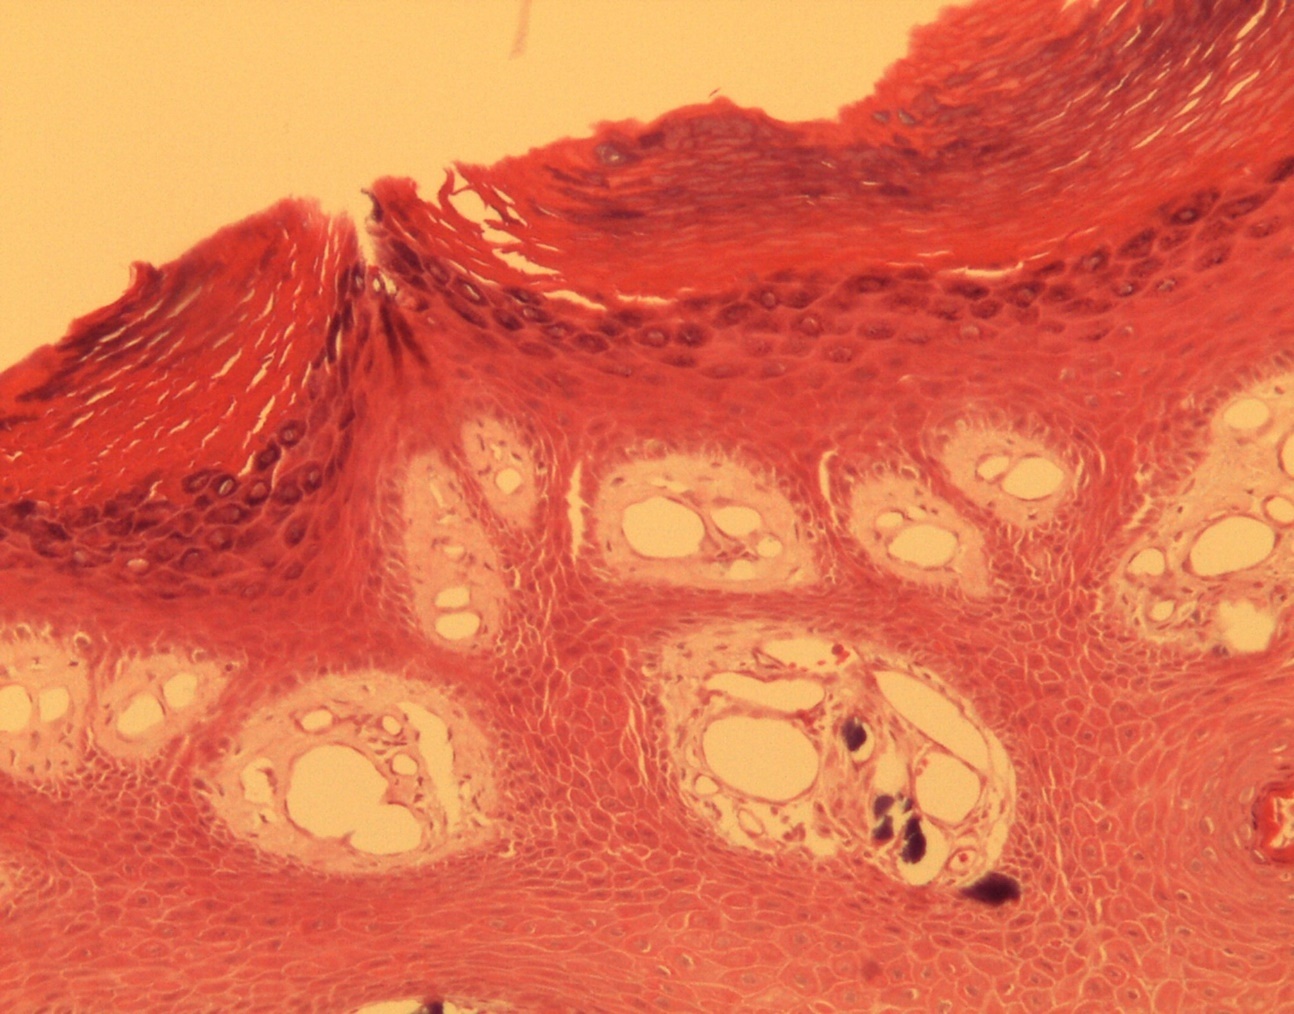

A 9-year-old male patient who was treated in the dermatology service for a progressively growing keratotic nummular dermal lesion on the right knee. With the clinical judgment of viral wart, the lesion was removed. In the Pathology Service, a nummular keratotic lesion of 0.5 cm in maximum dimensions was received, which crackled when cut. Figure 1, Figure 2, Figure 3, Figure 4, Figure 5

Figure 4.Presence of calcium deposits in the dermal vessels. Detail. HE 400x.

Calcinosis cutis refers to the deposit of calcium salts on the skin. It generally constitutes a morphological type of dystrophic calcium deposit, related to different types of lesions or injured tissues (in this case a common wart) without alterations in calcium metabolism in biochemical studies, typical of metastatic calcifications.

At an early age, like that of our patient, it is possible to make wrong clinical diagnoses, mainly that of pilomatricoma, a lesion with which it is necessary to make a clinical, but not histological, diagnosis. It is always advisable to carry out a measurement of calcium levels to rule out other scenarios.